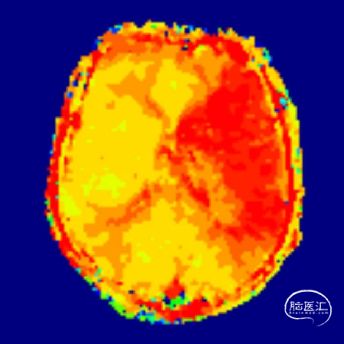

术后即刻影像。

支架植入后造影提示残余狭窄约10%。术中患者生命体征稳定,术后患者恢复良好出院,继续抗血小板聚集及他汀类药物治疗。